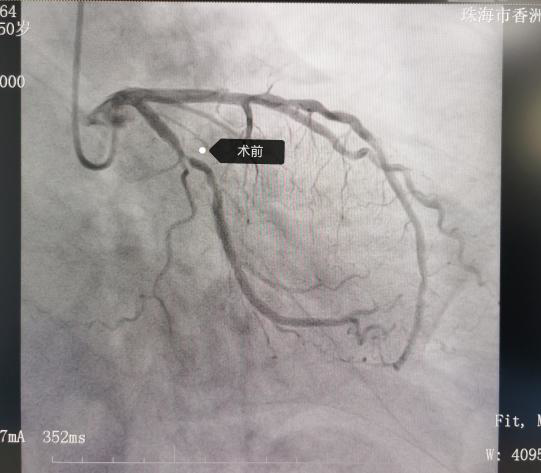

患者王某某,因反复胸闷1年余,加重2天入院。冠脉造影示:右优势型冠脉,左主干无狭窄,前降支近中段弥漫性狭窄30%~50%,第一对角支开口狭窄70%,回旋支近中段狭窄90%伴轻度钙化,右冠中段狭窄20%,各支TIMI血流均为3级。

为了精准介入治疗,心血管代谢医学科李绍波介入团队在IVUS指导下行冠脉支架植入术。IVUS示回旋支近中段轻度钙化,最窄处MLA1.86mm²,斑块负荷78%。于该处植入2.75×25mm药物洗脱支架一枚,高压球囊扩张后复查IVUS示支架膨胀及贴壁良好,无撕裂夹层,MLA增至6.05mm²。手术成功进行,患者症状缓解,已顺利出院。